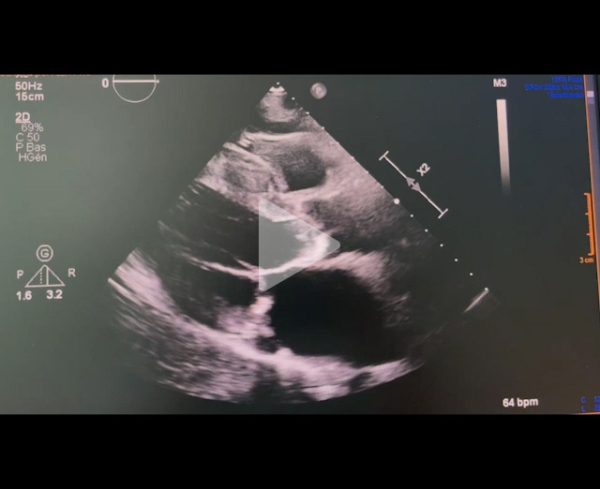

Echographie cardiaque transthoracique : PSGGA

Vidéo 1

Vidéo 2

Paramètres échographiques